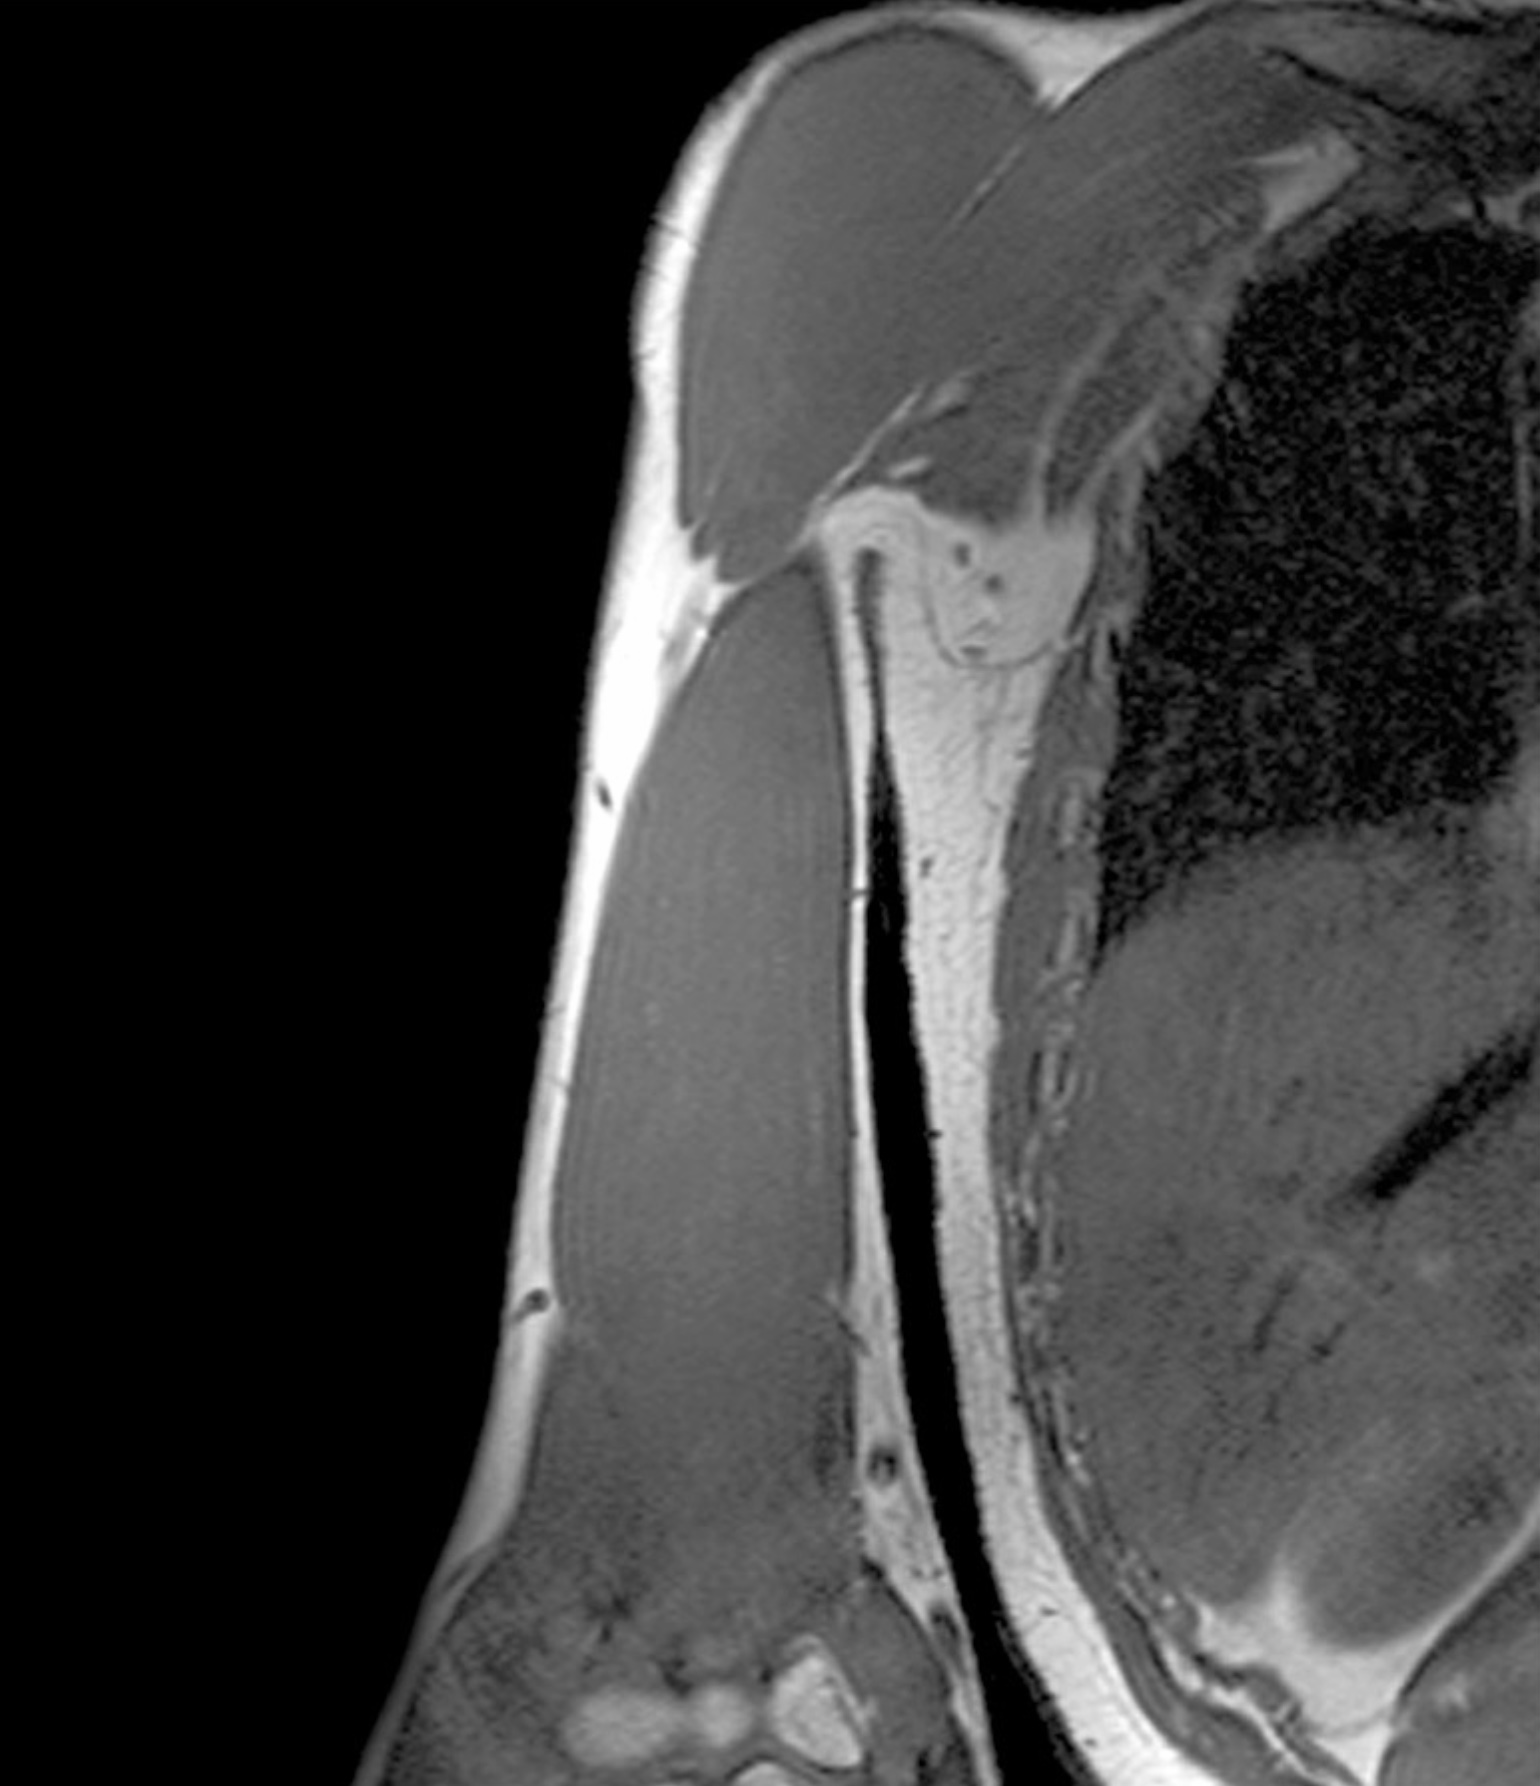

1. A patient complains of shoulder pain and difficulty rotating their arm. An ultrasound reveals edema within the spinoglenoid notch, which could explain weakness in external rotation at the glenohumeral joint. Describe the normal scapular and shoulder anastomosis, including all arterial branches involved and their relationship to any ligaments, scapula borders, and intermuscular spaces. If the axillary a. is ligated immediately distal to the thyrocervical trunk, would this edema affect active collateral circulation? (If yes, explain.) Also, include a brief (2-3 sentences) explanation for why edema within the spinoglenoid notch might result in weak external/lateral rotation of the shoulder.

2. A 27-year old patient suffers a humeral shaft fracture at the radial groove. Discuss the anatomy of the posterior compartment of the arm, including boundaries, contents, musculature, vascular supply, innervation, lymphatics and relationships. Differentiate between motor deficits of posterior arm and posterior forearm musculature relative to branching of the radial nerve superior and inferior to the radial groove.